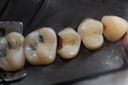

Kyle Chock #2 pre-op

Kyle Chock #2 caries removal

Kyle Chock #2 prep

Kyle Chock #2 finish